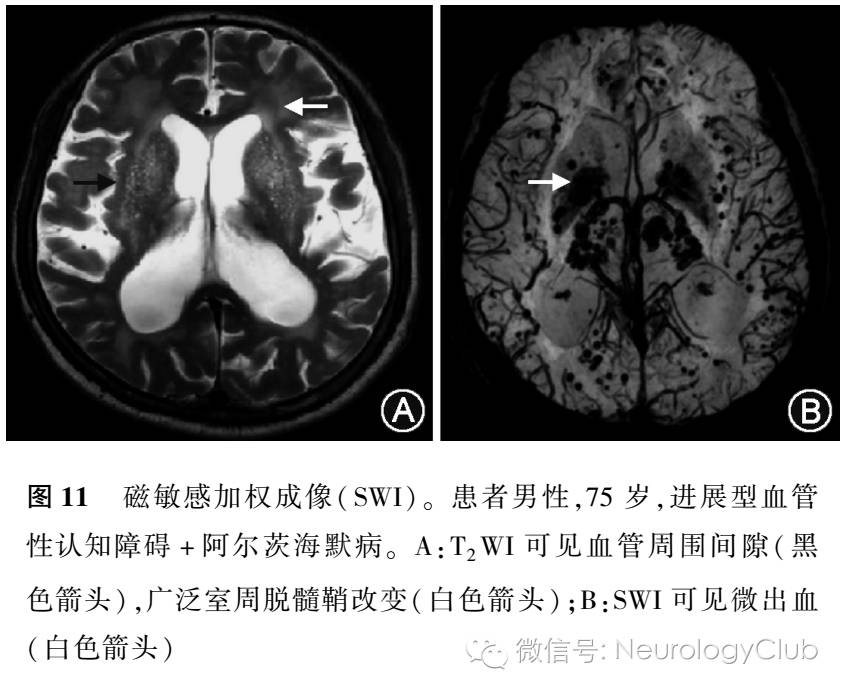

SWI是一项新的对组织磁化率差异及血氧水平依赖效应敏感的对比增强技术,采用三维采集、薄层重建、完全流动补偿及长回波时间的梯度回波序列(图11)。SWI序列,可早期诊断脑出血、发现缺血性脑卒中出血转化及微出血,为缺血性脑卒中血流动力学改变提供信息。SWI对于出血性转化敏感,有研究认为其检出自发性出血性转化能力早于CT。Huang等的一项纳入44例患者的研究表明,14例SWI检出微出血,19例检出磁敏感血管征。

静脉血栓形成在SWI图上能有很好的检出率,尤其是皮质静脉及静脉窦血栓形成。SWI 序列检出1-3d内的静脉窦或静脉血栓形成的敏感度分别为90%。

2011年,Ayaz等研究轻度认知功能障碍患者,利用SWI检出了直径1mm的脑微出血。2014年的一项荟萃分析表明,相位成像(phase-sensitive imaging)或者SWI较T2WI检测脑微出血更为合适,并用该序列长期评估脑微出血可以更好地控制管理烟雾病。